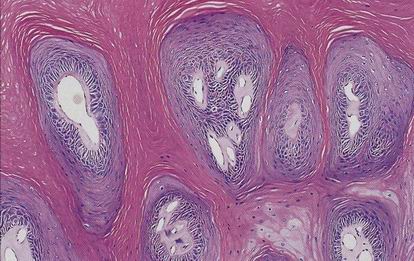

Verrucous carcinoma

Varianta spinoca s velmi dobrou prognózou

Definován

verukózním růstem

minimálním stupněm cytologické atypie

ostře ohraničeným růstem proti spodině (byť může infiltrovat hluboko)

Diagnózu VC z probatorní excize není možno podle uvedené definice stanovit, lze jen vyslovit suspekci.